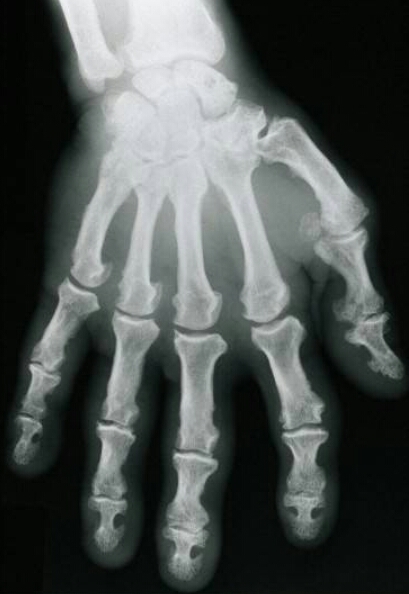

What is the diagnosis? What radiographic features are present?

acromegaly

spade-like distal tufts, hooking osteophytes, increased joint spaces initially, widened shaft, increased tissue thickness